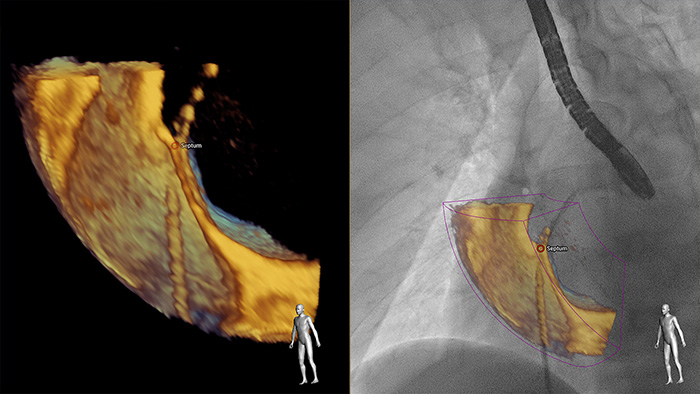

Greater insight and confidence in finding and treating the problem through SmartFusion. EchoNavigator automatically fuses live 3D TEE and live X-ray in real time so you can intuitively guide your device in the 3D space more quickly.